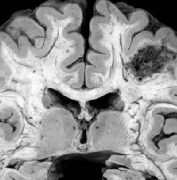

人脑动静脉畸形 (脑动静脉畸形)是大脑循环系统的缺陷,通常认为是在胚胎或胎儿发育过程中出现的。通常,含氧血液由心脏通过分支动脉(称为动脉)...

脑动静脉畸形 (AVMs)是血管系统的缺陷,由异常血管缠结(nidus)组成,其中供血动脉在没有毛细血管床的介入下,直接连接到静脉引流网络。动脉将富含氧气...

脑动静脉畸形(BAVM)是指一组异常的脑血管,包括供血动脉、引流静脉和中间的异常血管集合,称为nidus。淋巴结的血管通常被称为毛细血管,但组织学检...